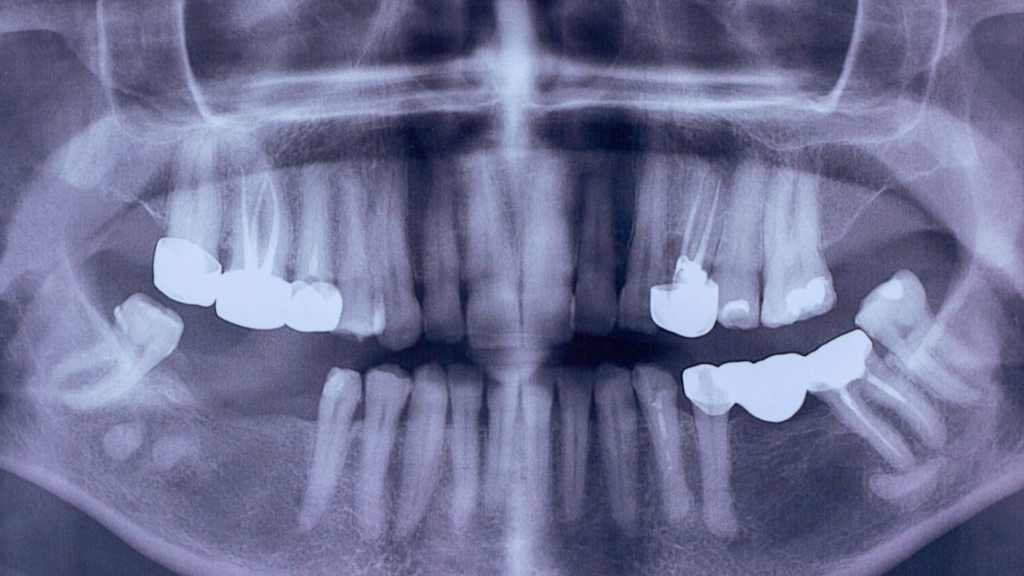

Zähne als unterschätzte Quelle chronischer Schmerzen

Im schmerztherapeutischen Alltag begegnen mir immer wieder Menschen, die trotz zahlreicher Untersuchungen keine klare Erklärung für ihre Beschwerden finden. Die Diagnostik […]